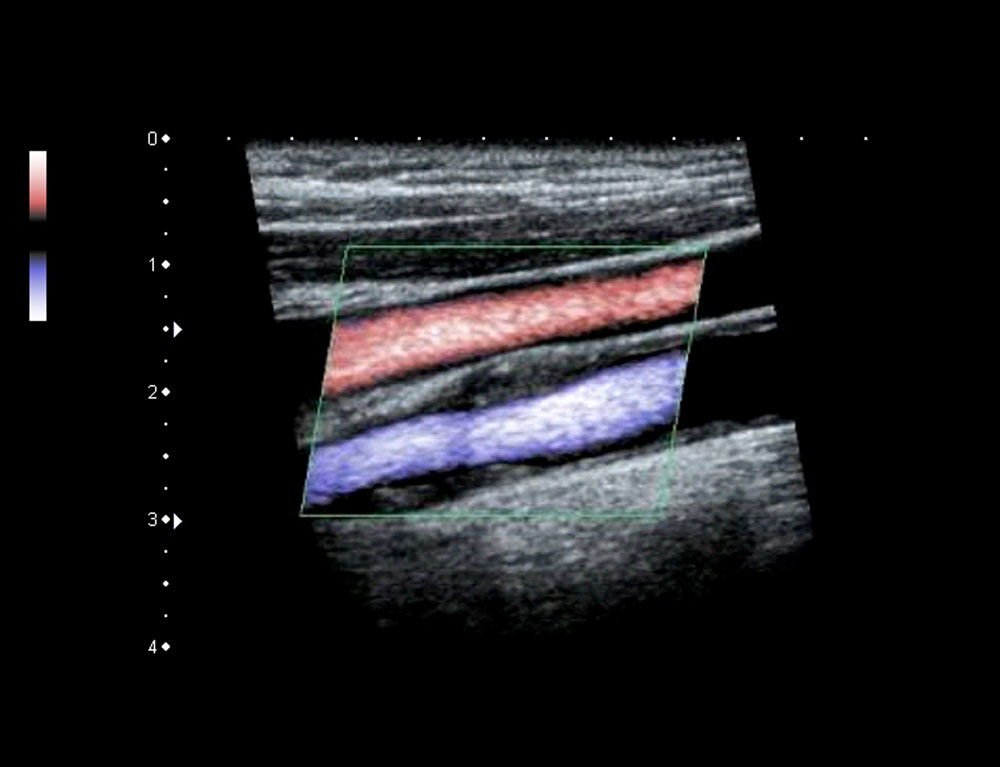

True Hemodynamic Flow.

Advanced Dynamic Flow™ (ADF)*

Canon Medical Systems' exclusive ADF technology provides highly detailed Color Doppler resolution at high frame rates for high resolution of the small blood vessels and complex blood flow with amazing clarity.

*Available on all current systems.

ADF on the Carotid Artery and Jugular Vein simultaneously